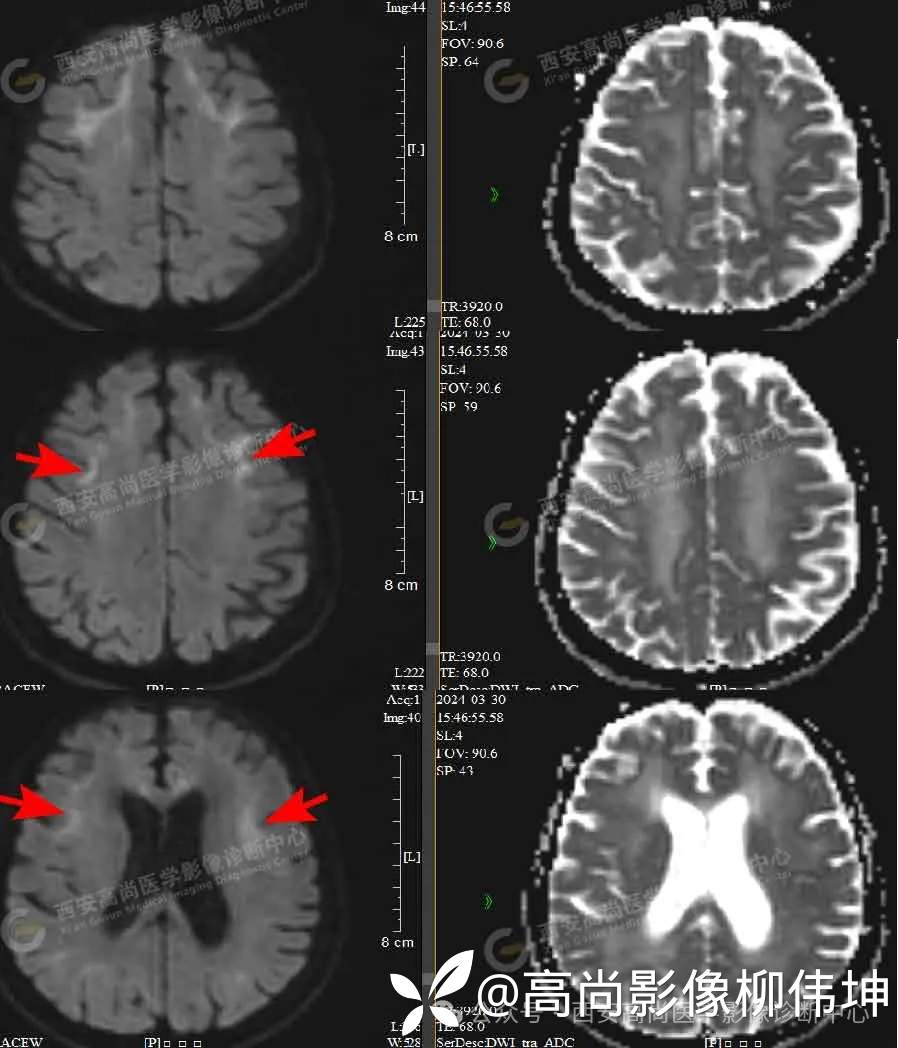

MR影像图

横轴位 T2WI 横轴位 FLAIR 横轴位 T1WI

DWI ADC

MR平扫+DWI+MRS:双侧额叶、半卵圆中心、侧脑室旁、胼胝体白质区见片状稍长T1稍长T2信号,FLAIR像显示高信号,边缘模糊,DWI像上病灶边缘见条片状高信号,ADC图上呈稍低信号,MRS示:上述病灶CHO波未见增高,NAA波未见减低,CHO/NAA为0.58。

诊断:双侧额叶、半卵圆中心、侧脑室旁、胼胝体区对称性脑白质脱髓鞘,考虑神经元核内包涵体病可能。

影像表现:皮髓质交界区广泛DWI鸡冠花样、曲线样高信号、胼胝体DWI高信号、对称性脑白质病变、皮层肿胀、广泛性脑萎缩。

(1)皮髓质交界区曲线样DWI高信号

为从额顶颞叶皮髓质交界区开始,随着病情发展向大脑后部延伸,形成皮质下“鸡冠花样”或“绸带征”的DWI高信号(具有一定的特异性,病理证实为海绵样变)。家系NID患者仅有37.5%出现上述DWI改变。

(2)胼胝体DWI高信号

部分患者在病程早期仅出现胼胝体的DWI高信号,提示胼胝体联络纤维和皮质下弓形纤维具有类似的易受累性。需要和可逆性胼胝体压部脑病、Marchiafava-Bignami综合征进行鉴别。